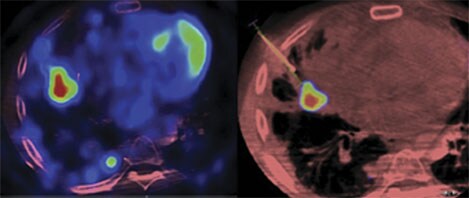

XperGuide Ablation: treatment planning and live needle guidance

What EmboGuide does for embolization, XperGuide Ablation does for percutaneous ablation procedures. It allows reliable and accurate needle interventions for tumor biopsies and ablations, even for locations that are small and hard to reach, at a low dose. In the segmentation step, one or more lesions can be visualized and segmented. Then, the planning step allows you to plan the treatment, showing one or more needle paths for radiofrequency, microwave or cryo-ablation antennas. The tool visualizes specific needle isotherms in relation to the patient’s anatomy to help reduce the risk of compromising adjacent organs. During the procedure, Live Image Guidance feature shows the path of the needles and real-time antenna position, allowing clinicians to course-correct and guide the needle to the target position.